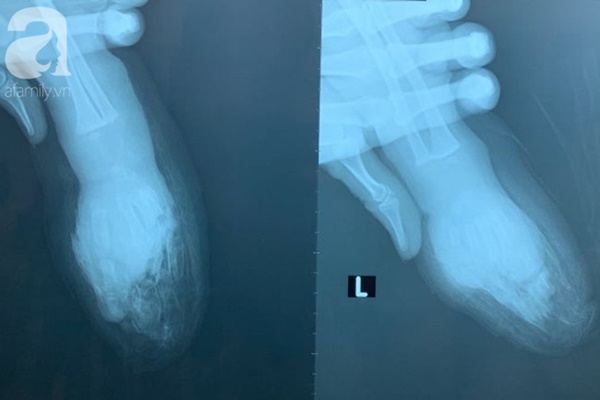

Ảnh chụp phim 2 bên bàn tay bé.

Nạn nhân là bé T.Đ.K. (1 tuổi, quê Đồng Tháp) được chuyển từ một bệnh viện chuyên khoa nhi ở TP.HCM trong tình trạng ngón 2, 3, 4, 5 tay trái bị đứt lìa, bàn tay trái bị đứt ngang ở giữa, đứt lìa đốt ngón trỏ bàn tay phải, đã được sơ cứu.

4 ngón tay của bé bị đứt lìa sau tai nạn.